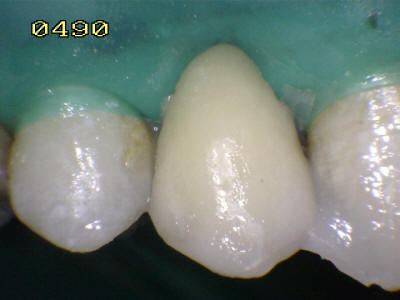

Aislación absoluta con dique de goma

Grabado con ácido ortofosfórico

Flechas rojas: Esmalte grabado   Flechas azul resina compuesta